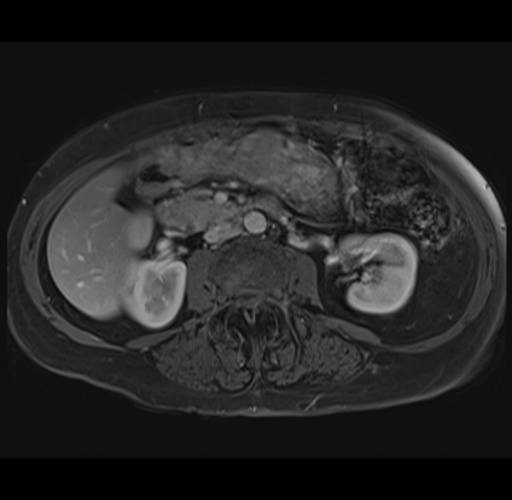

MRI T1